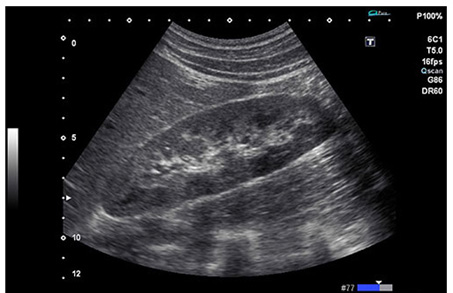

O Hospital de Equinos é o primeiro do Brasil a utilizar esse aparelho. Indicado pela Universal Imaging como um dos 5 melhores aparelhos de ultrassonografia para uso em equinos, ele alia portabilidade com uma qualidade de imagem superior. Com tela totalmente TouchScreen, podemos oferecer aos nossos pacientes um novo nível de diagnóstico, graças á nova tecnologia e aos vários aplicativos que o VIAMO nos oferece, incluindo o ApliPure, uma nova tecnologia de obtenção de imagem presente nos melhores aparelhos de Ultrassonografia do mundo.